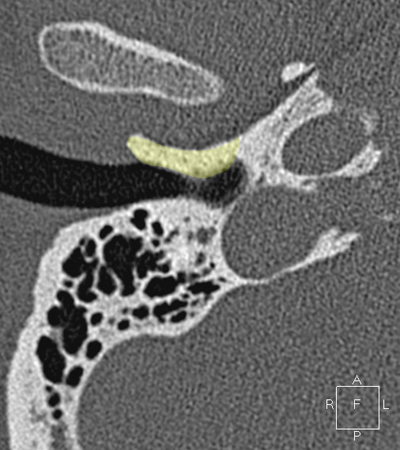

Sigmoid sinus Jugula bulb Horizontal petrous carotid Groove for tympanic (Jacobson's) nerve Facial nerve (f3), mastoid segment Anterious wall of bony EAC (tympanic bone) Mandibular condyle